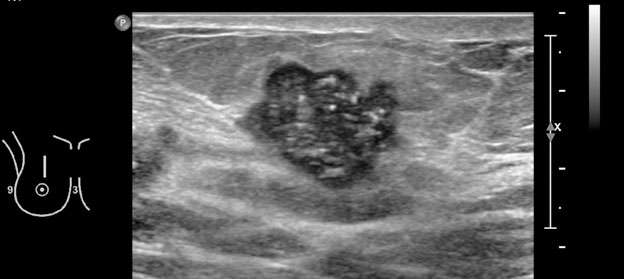

Figure 4: Microlobulated right breast mass, containing calcifications, at 12:00 position 5 cm from nipple, BI-RADS CATEGORY 5 - SUSPICIOUS ABNORMALITY, ultrasound guided biopsy was recommended. Pathology confirmed invasive ductal carcinoma, Grade 3.